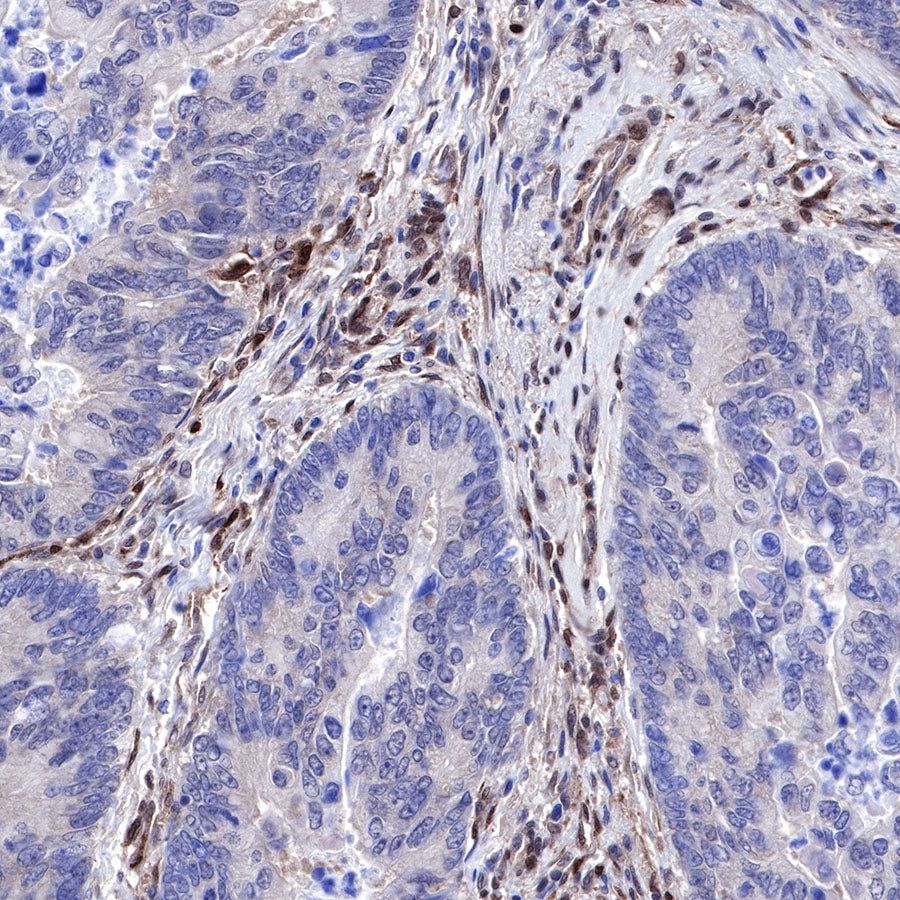

Immunohistochemistry

IHC shows positive staining in paraffin-embedded human colon cancer. Anti-PTEN antibody was used at 1/500 dilution, followed by a HRP Polymer for Mouse & Rabbit IgG (ready to use). Counterstained with hematoxylin. Heat mediated antigen retrieval with Tris/EDTA buffer pH9.0 was performed before commencing with IHC staining protocol.